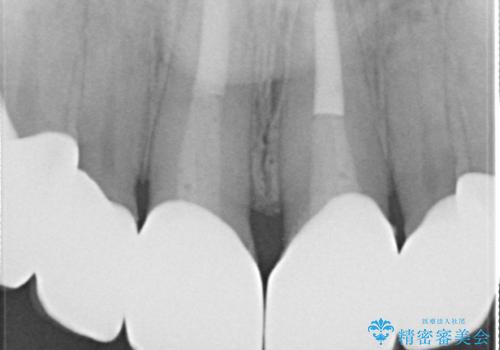

- 昔装着した前歯のかぶせ物を新しくしたいとのことで来院されました。

ご自身の歯とかぶせ物の境目が露出しておりました。

前歯の合計6本をオールセラミッククラウンにする計画としました。